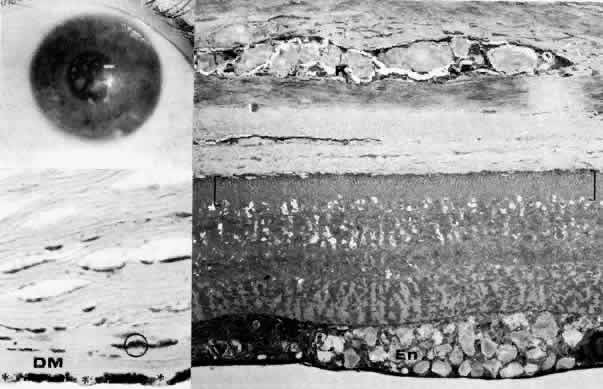

Fig. 11. Macular corneal dystrophy. Top left. Clinical appearance of cornea features diffuse haze extending to the limbus with superimposed, dense gray-white spots. Bottom left. Light photomicrograph of posterior cornea shows endothelial cells staining intensely positive for acid mucopolysaccharide. Guttate excrescences (*) of Descemet's membrane (DM) are frequent. The stroma also shows positive staining for acid mucopolysaccharide both diffusely extracellularly and intensely within keratocytes (circled) (colloidal iron × 500). Right. Transmission electron micrograph discloses typical fibrillary granular deposits within keratocytes (K), throughout the posterior layer of Descemet's membrane, and within the endothelial cells (En). The anterior banded region of Descemet's membrane (bracketed) is not affected (× 3500).

The lesions in macular corneal dystrophy stain intensely with alcian blue and colloidal iron, minimally with PAS, and not at all with Masson's trichrome. Birefringence is decreased. The lesions have been histochemically identified as an abnormal keratan sulfate-like glycosaminoglycan that accumulates extracellularly within the stroma and Descemet's membrane and intracellularly within keratocytes and endothelium.130

As would be typical of an autosomal recessively inherited condition, macular dystrophy presumably results from deficiency of a hydrolytic enzymes (sulfotransferase) and may thus be considered a localized mucopolysaccharidosis.131 The effect of altered glycosaminoglycan metabolism is evident at the cellular level; on transmission electron microscopy, keratocytes and endothelial cells exhibit distention of rough-surfaced endoplasmic reticulum cisternae. With the acridine orange technique, compensatory generalized hyperactivity of the lysosomal enzyme system has been demonstrated.132 Eventually the accumulated undigested storage products engorge the cells, and the cells ultimately degenerate or rupture. The derivation of these intracytoplasmic storage vacuoles from endoplasmic reticulum suggests that the biochemical lesion in macular dystrophy occurs at a different metabolic location than in the systemic mucopolysaccharidoses, since in the latter, storage products accumulate within lysosomelike intracytoplasmic vacuoles associated with the Golgi complex.133 Snip and associates134 were able to determine that the storage phenomenon affecting endothelium and Descemet's membrane is likely also primary, since the intracellular and extracellular lesions appear ultrastructurally comparable to those evident in the keratocytes and stroma.

Fig. 15. Congenital hereditary endothelial dystrophy. Top left. Clinical photograph of eye of a 14-year-old male with severe form of the dystrophy shows diffuse ground-glass stromal opacification. Top middle. In a mildly affected 20-year-old female, the cornea has moderate diffuse haze and visual acuity is 20/200. Top right. On slit lamp biomicroscopy, diffuse edematous thickening of the corneal stroma is evident in same patient as top middle photograph. Middle right. Light microscopy of a case with uniformly thickened (approximately 35μm) Descemet's membrane (DM) covered posteriorly by extremely attenuated endothelial cells (arrowheads). S, posterior stroma; AC, anterior chamber (hematoxylin-eosin, × 600). Bottom left. Transmission electron micrograph of same case as middle right micrograph reveals anterior portion of Descemet's membrane (DM) to have normal thickness and banded structure. The markedly thickened (approximately 20 μm) posterior layer exhibits both 55 nm and 110 nm banding (circled) interspersed with homogeneous material. En, endothelial cell; AC, anterior chamber; S, posterior stroma (× 9200). Bottom right. At higher magnification, the abnormal posterior zone is seen to consist of multiple laminations of basement membrane-like material (*) and fine filaments. En, endothelial (× 42,000).

The degree of edematous corneal clouding varies from a mild haze to a milky, ground-glass opacification. Epithelial microbullae may be obvious, and stromal thickness may be increased threefold or more. Uniform thickening of Descemet's membrane is sometimes evident on clinical examination, but no guttata are apparent. Interstitial inflammation and secondary vascularization are absent. There are no definitely associated ocular or systemic abnormalities.

Histologic study175–181 reveals nonspecific anterior and stromal changes consistent with long-standing secondary edema: basal epithelial cell swelling, basement membrane thickening and disruptions, and irregularities of Bowman's layer with pannus formation. However, it may be significant that, in some cases, ultrastructural examination discloses greatly enlarged stromal collagen fibrils sometimes measuring as much as 60 nm in diameter. Descemet's membrane is uniform in a given specimen; it may display diffuse thinning of 3μm to massive thickening of 40 μm (normal thickness is 3 to 5 μm in neonates and 8 to 10 μm in adults). The anterior banded layer of Descemets membrane is always present and of relatively usual thickness; however, the posterior layer consists of multilaminar basement membrane-like material with fine filaments and of collagen fibrils with a 55- and 110-nm banded configuration. With the exception of the lack of guttata, these findings are similar to those in Fuchs' dystrophy and thus represent another example of posterior collagen layer formation by either primarily or secondarily abnormal endothelium.18,41,43,181, It is postulated that in cases with thin Descemet's membrane, complete endothelial loss occurred in utero such that only the fetal anterior portion of Descemet's membrane was secreted.180 In contrast, cases exhibiting thickened Descemet's membranes may be the product of dystrophic but persistent endothelium having secreted a hypertrophic posterior collagen layer.